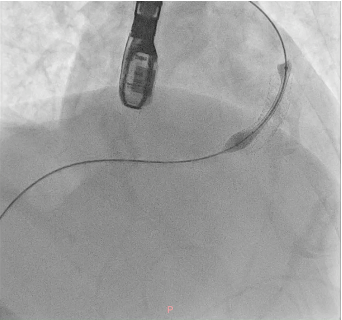

A soft hydrophilic 0.035-inch wire was directed into the RVOT, advanced distally to the right pulmonary artery, then exchanged for a super stiff 0.035-inch wire. An Armada vascular balloon 7.0x60 mm was positioned in the RVOT and inflated to 12 atm for ten cycles. An Omnilink vascular stent was deployed in the RVOT and inflated to 12 atm. Due to the patient¡¯s late presentation, a second identical stent was placed at the same location. Following the procedure, LVEF improved to 64.7%, and aortic oxygen saturation increased from 86% to 94%.